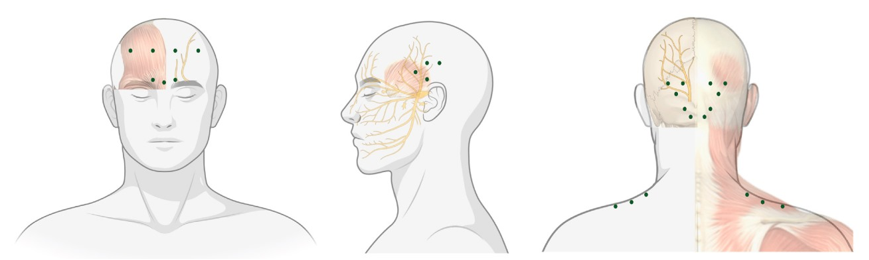

– Aplicação de toxina botulínica: para cefaleias e espasticidade, por exemplo

FONTE: Ray JC, Hutton EJ, Matharu M. OnabotulinumtoxinA in Migraine: A Review of the Literature and Factors Associated with

Efficacy. Journal of Clinical Medicine. 2021; 10(13):2898.